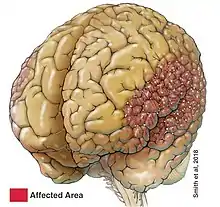

Polymicrogyria (PMG) is a condition that affects the development of the human brain by multiple small gyri (microgyri) creating excessive folding of the brain leading to an abnormally thick cortex. This abnormality can affect either one region of the brain or multiple regions.

The main patterns of polymicrogyria are: perisylvian (61%), generalised (13%), frontal (5%), and parasagittal parieto-occipital (3%) and 11% is associated with gray matter heterotopia (grey matter is located in the white matter instead of usual location in the cerebral cortex).[1]

Bilateral perisylvian polymicrogyria (BPP)

BPP is similar to the other types of polymicrogyria in that it is usually symmetrical, but BPP can vary among patients. BPP is characterized by its location; the cerebral cortex deep in the sylvian fissures is thickened and abnormally infolded, as well as the sylvian fissures extending more posteriorly up to the parietal lobes and more vertically oriented.[2] BPP has been classified into a grading system consisting of four different grades that describe the variations in severity: